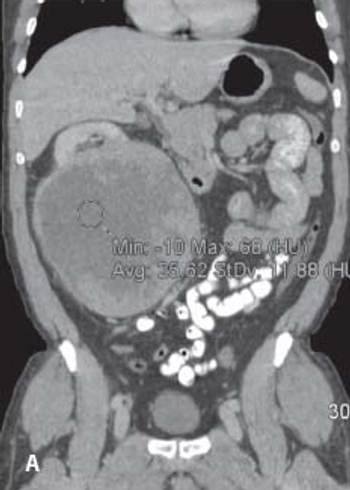

Image-guided radiofrequency ablation may be an effective alternative treatment for small renal cell carcinoma tumors, according to the results of a recent study.